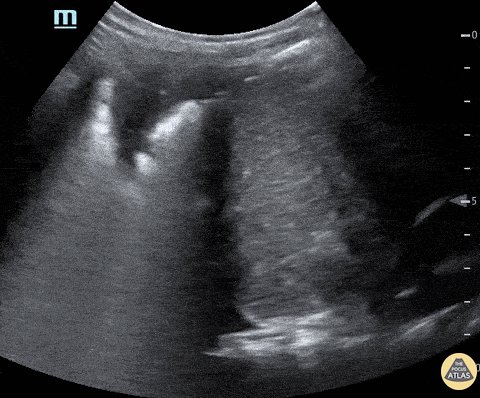

16 - Ascites